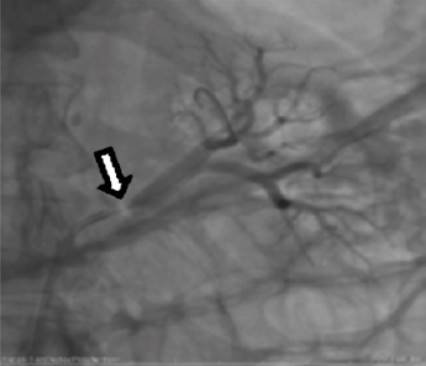

En vista de estos hallazgos, se trató como displasia fibromuscular y se procedió a realizar angioplastia bilateral. Primero de la arteria renal izquierda, predilatándose con un balón 6.0 x 20 mm e implantándose a seguir una endoprótesis vascular de 7.0 x 12 mm sin lesión residual y con flujo normal. Se canuló la arteria renal derecha superior entregándose una endoprótesis vascular directa 5.0 x 12 mm sin lesión residual con flujo normal. Posteriormente se canuló la arterial renal derecha inferior entregándose otra endoprótesis vascular directa de 3.5 x 20 mm sin lesión residual pero con espasmo posterior a la endoprótesis que cedió con 200 µg de nitroglicerina, concluyendo el procedimiento sin complicaciones (Figura 3).

Figura 3 A. Permeabilización con endoprótesis vascular de la arteria renal derecha (principal y accesoria). B. Permeabilización con endoprótesis vascular de la arteria renal izquierda (flecha).